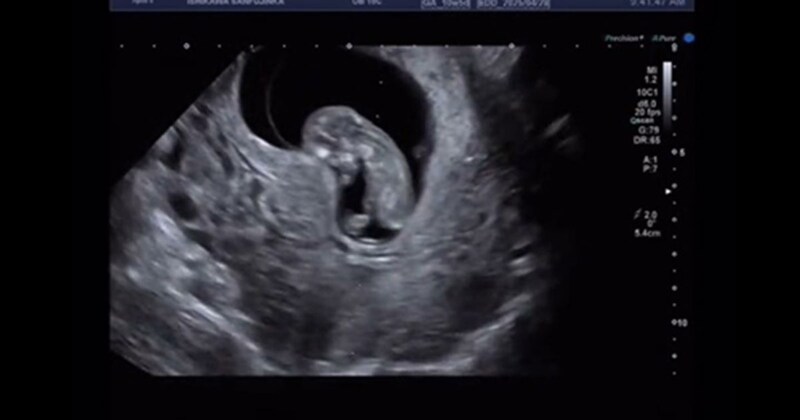

投稿者は、TikTokユーザーのHOSHINO USAGI(@usagichan.08)さん。子育て中のママで、お子さんとの日常を発信しています。2025年7月には、妊娠10週目のときの次女ちゃんのエコー動画がTikTokで話題を集めました。

その動画では、うずくまるような姿勢から上に向かって何度もジャンプ! ぴょんぴょん飛び跳ねるように動いており、生まれる前から元気いっぱいなのが伝わってきます。

元気すぎるエコー動画は「CGじゃない?」とよく言われたそうで、ママがTikTokに投稿したところ23万回以上の再生数を記録。「え?!ほんもののエコーですか?」「自己主張の強い胎児映像を初めて見ました!」「奇跡だね」などの声が寄せられました。